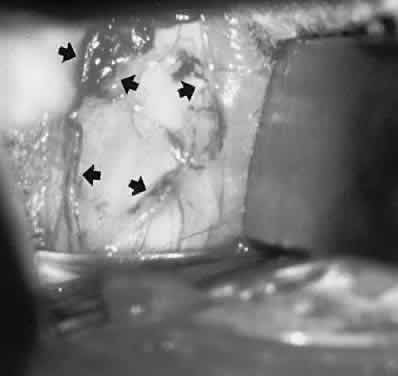

Fig. 23. Exposure of supraorbital vein (arrows) for endovascular interventional closure of cavernous sinus fistula.